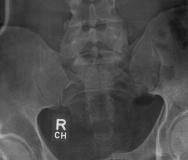

X-Rays and scans of the damaged right & left legs plus the pelvis

These x-rays were taken just after the accident. Some of the bones on the right leg have already been pushed back into the leg. The CT

scans show various views of the ankles and pelvis prior to any corrective surgery. Fibula bracing is clear in some of the images as well as

bracing that was used to secure the "open book" pelvis. In some of the last images it is apparent that the upper part of Liam’s left fibula is

broken. Liam was told that the pain he felt was most likely a muscle cramp. Nothing was done to repair this break and you will see in further

x-rays that the bone shifted and later fused in such a way as to add to the reduction of Liam’s leg length. The last photo shows the stint

used to block any potential blood clots from moving up.